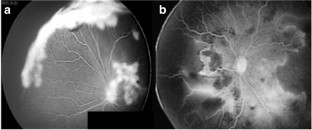

Retrospective chart review of all patients diagnosed with ROP1 initially treated with IVB in 6 tertiary referral centers of Toluca and Mexico City from 2005 to 2017. Treatment failure was defined as persistence or progression of neovascularization, elevation of the ridge, worsening of plus disease, or retinal crunch within the first week after treatment. Recurrence was defined as the new appearance of plus disease, an elevated ridge, or pathological new vessels after an initial regression of ROP following treatment. Therapy was observation, switch of anti-VEGF agent, retinal photocoagulation, vitrectomy, or a combination of two or more, depending on the severity of findings.

A total of 672 patients who received intravitreal bevacizumab injection for ROP1 treatment were included. Of these, 2.5% (17 patients) failed to treatment, 6.8% (46 patients) developed a recurrence for ROP, and 5.5% (37 patients) carried a misdiagnosis of recurrence and were diagnosed with other than ROP1 after examination. Based on the severity of findings, patients with recurrence or treatment failure were further treated by observation, repeat anti-VEGF intravitreal injection (bevacizumab or other), laser photocoagulation, vitrectomy, or a combination of these. Based on the treatment results, a therapeutic algorithm was created.